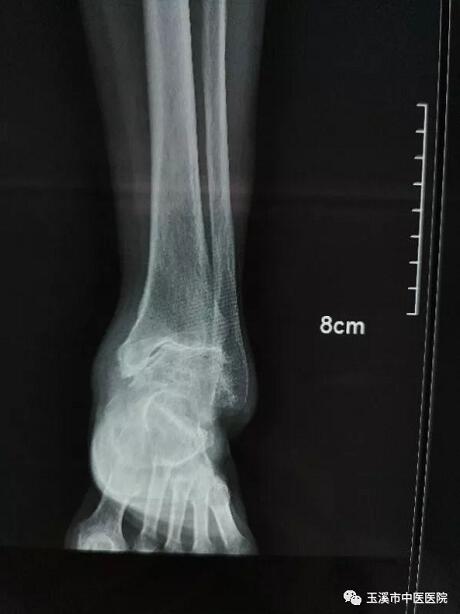

在醫(yī)務(wù)人員緊張的情況下,骨傷Ⅰ科克服種種困難,先后派出3名一線醫(yī)務(wù)人員赴千里之外的德欽縣人民醫(yī)院進(jìn)行對(duì)口援助。朱金富醫(yī)生是今年8月份去到藏區(qū)的,一到那里便積極投入工作。一位五十六歲藏族阿媽來到醫(yī)院看病時(shí),左踝關(guān)節(jié)疼痛、畸形三十余年了。 朱醫(yī)生將她收治入院,在相關(guān)檢查后,為她做了左踝關(guān)節(jié)融合術(shù)。術(shù)后藏族阿媽左踝關(guān)節(jié)功能明顯改善,生活及勞動(dòng)能力有所恢復(fù),一家人皆大歡喜。

術(shù)前X光片(左踝關(guān)節(jié)正位)